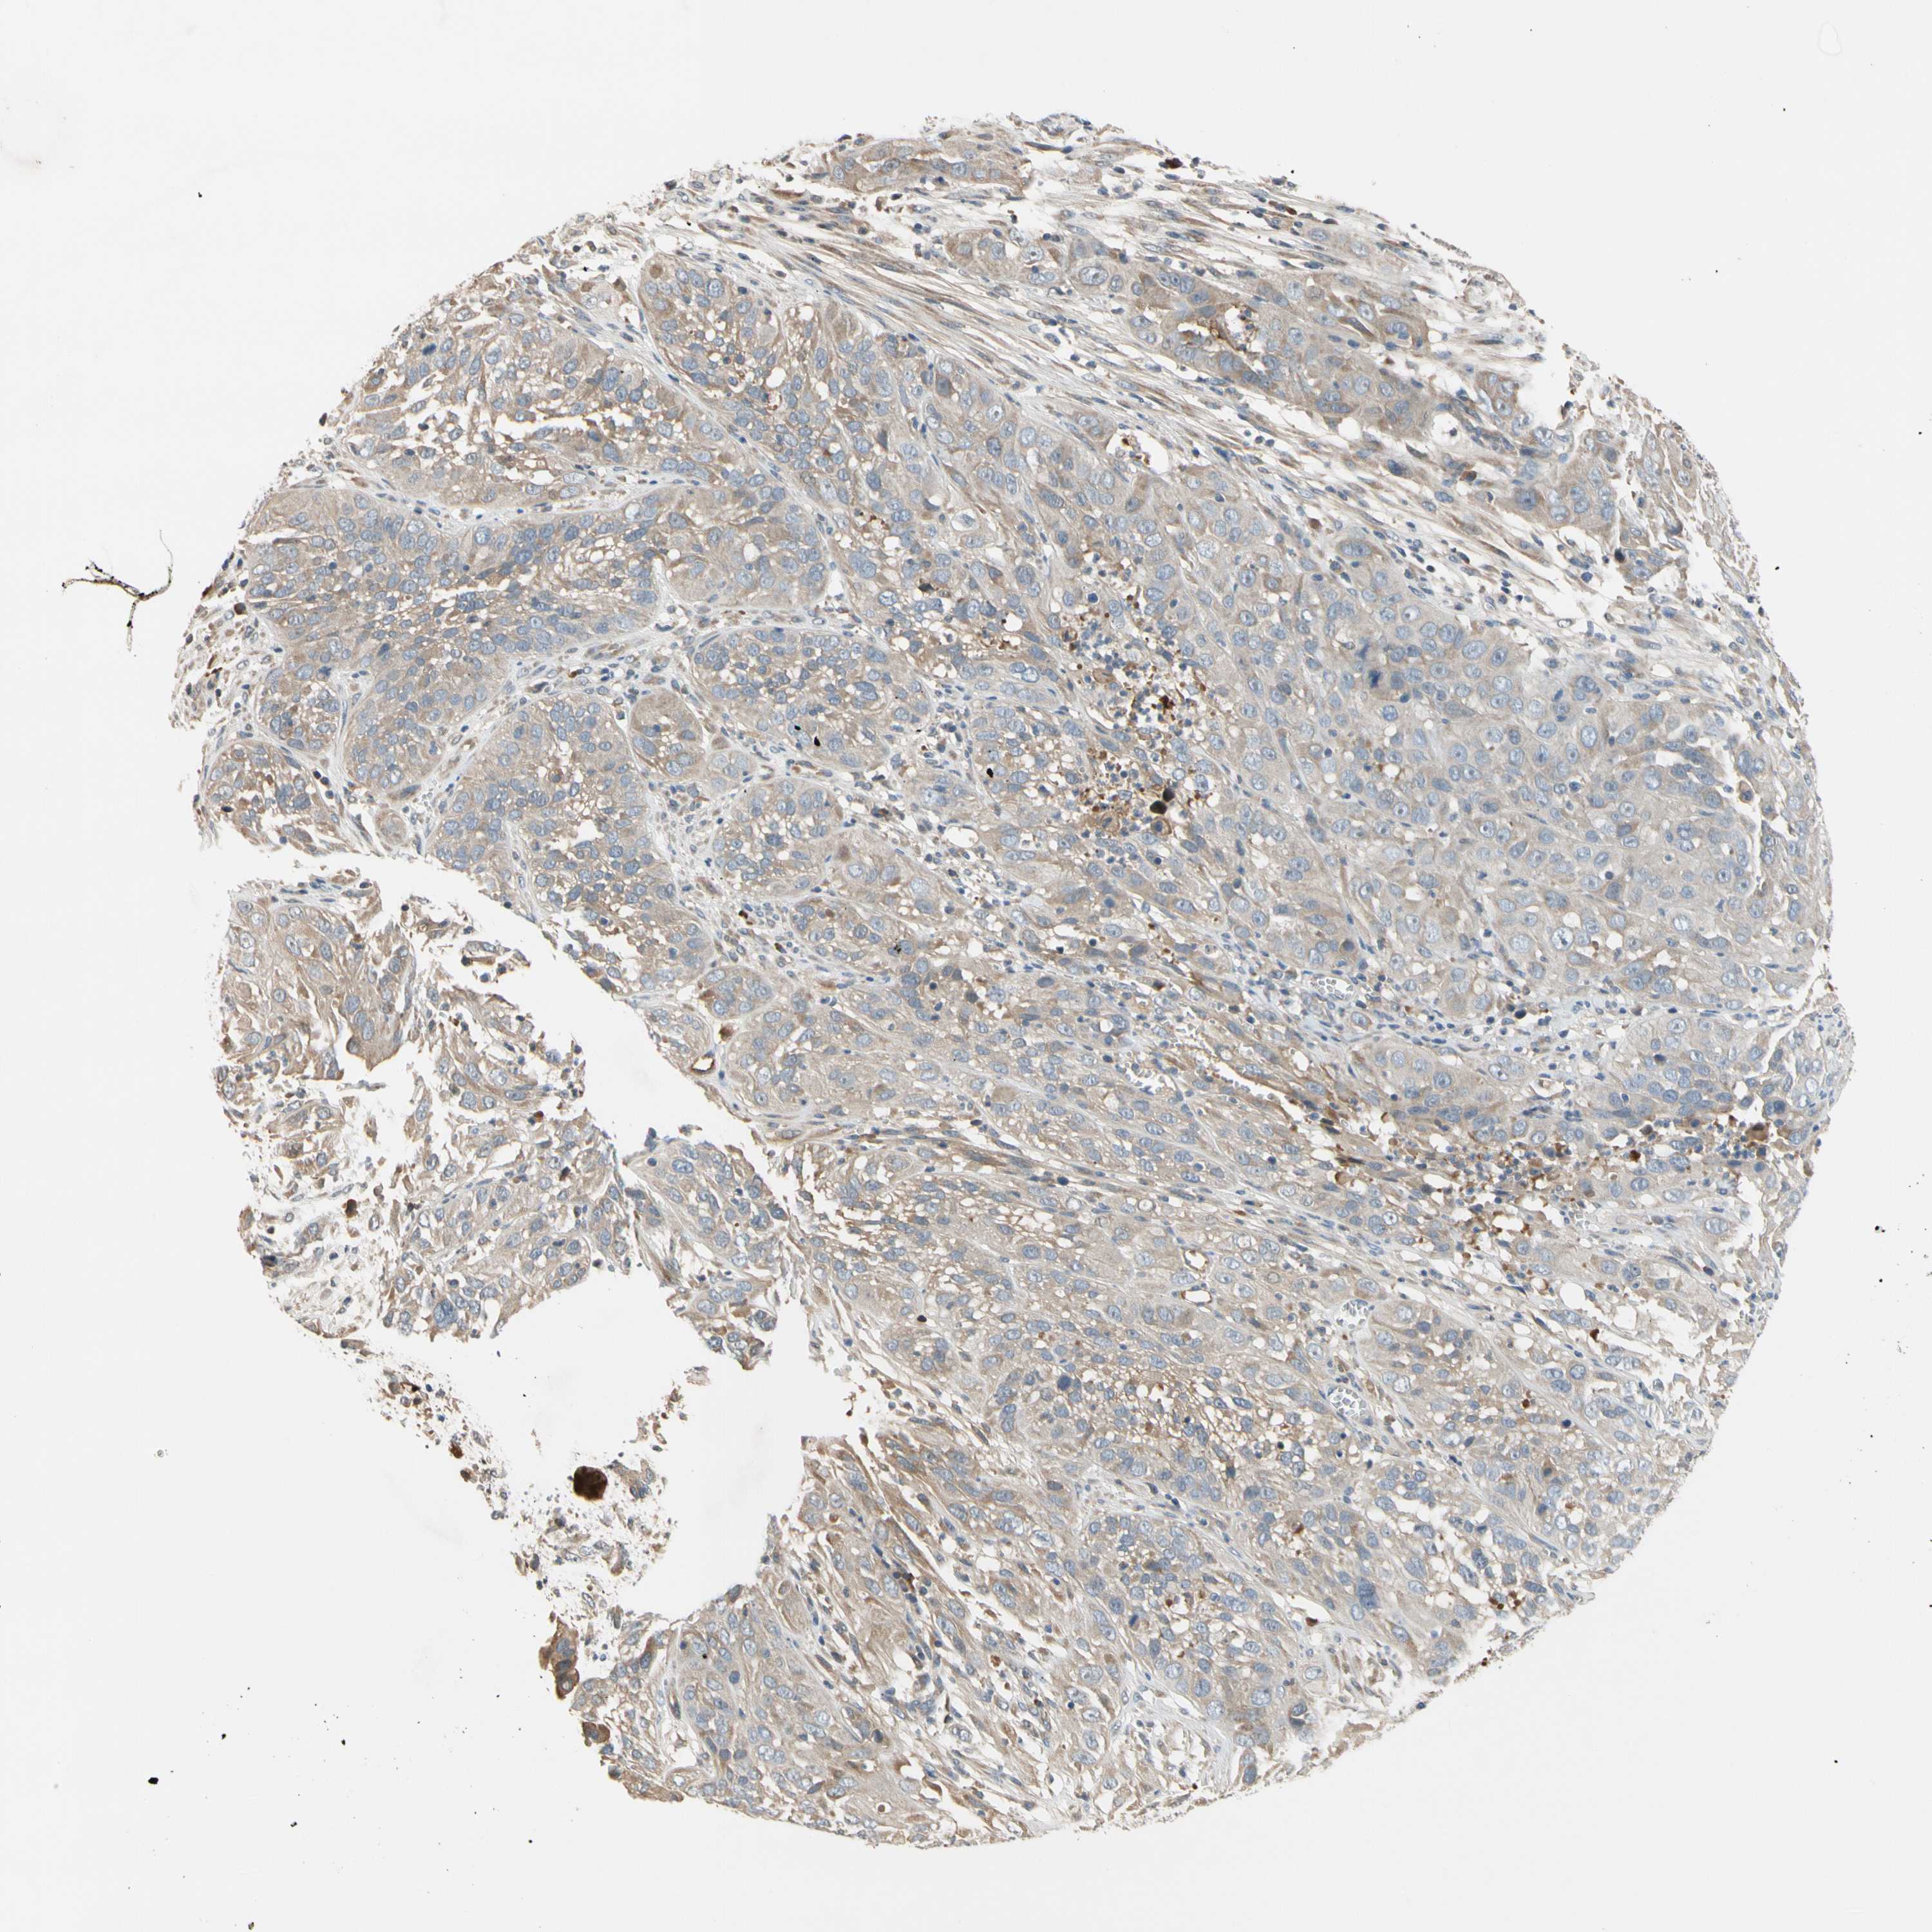

CERVICAL CANCER - Protein expressioni

A mouse-over function shows sample information and annotation data. Click on an image to view it in a full screen mode. Samples can be filtered based on level of antibody staining by selecting one or several of the following categories: high, medium, low and not detected. The assay and annotation is described here.

Note that samples used for immunohistochemistry by the Human Protein Atlas do not correspond to samples in the TCGA dataset.

Antibody stainingi

Antibody staining in the annotated cell types in the current human tissue is reported as not detected, low, medium, or high, based on conventional immunohistochemistry profiling in selected tissues. This score is based on the combination of the staining intensity and fraction of stained cells.

Each image is clickable and will lead to virtual microscopy that enables deeper exploration of all samples and also displays staining intensity scores, fraction scores and subcellular localization as well as patient and tissue information for each sample.

HPA046356

HPA048287

HPA050103

CAB009811

CAB032603

Staining

High

Medium

Low

Not detected

Intensity

Strong

Moderate

Weak

Negative

Quantity

>75%

75%-25%

<25%

None

Location

Nuclear

Cytoplasmic/membranous

Cytoplasmic/membranous,nuclear

Squamous cell carcinoma, NOS

Adenocarcinoma, NOS